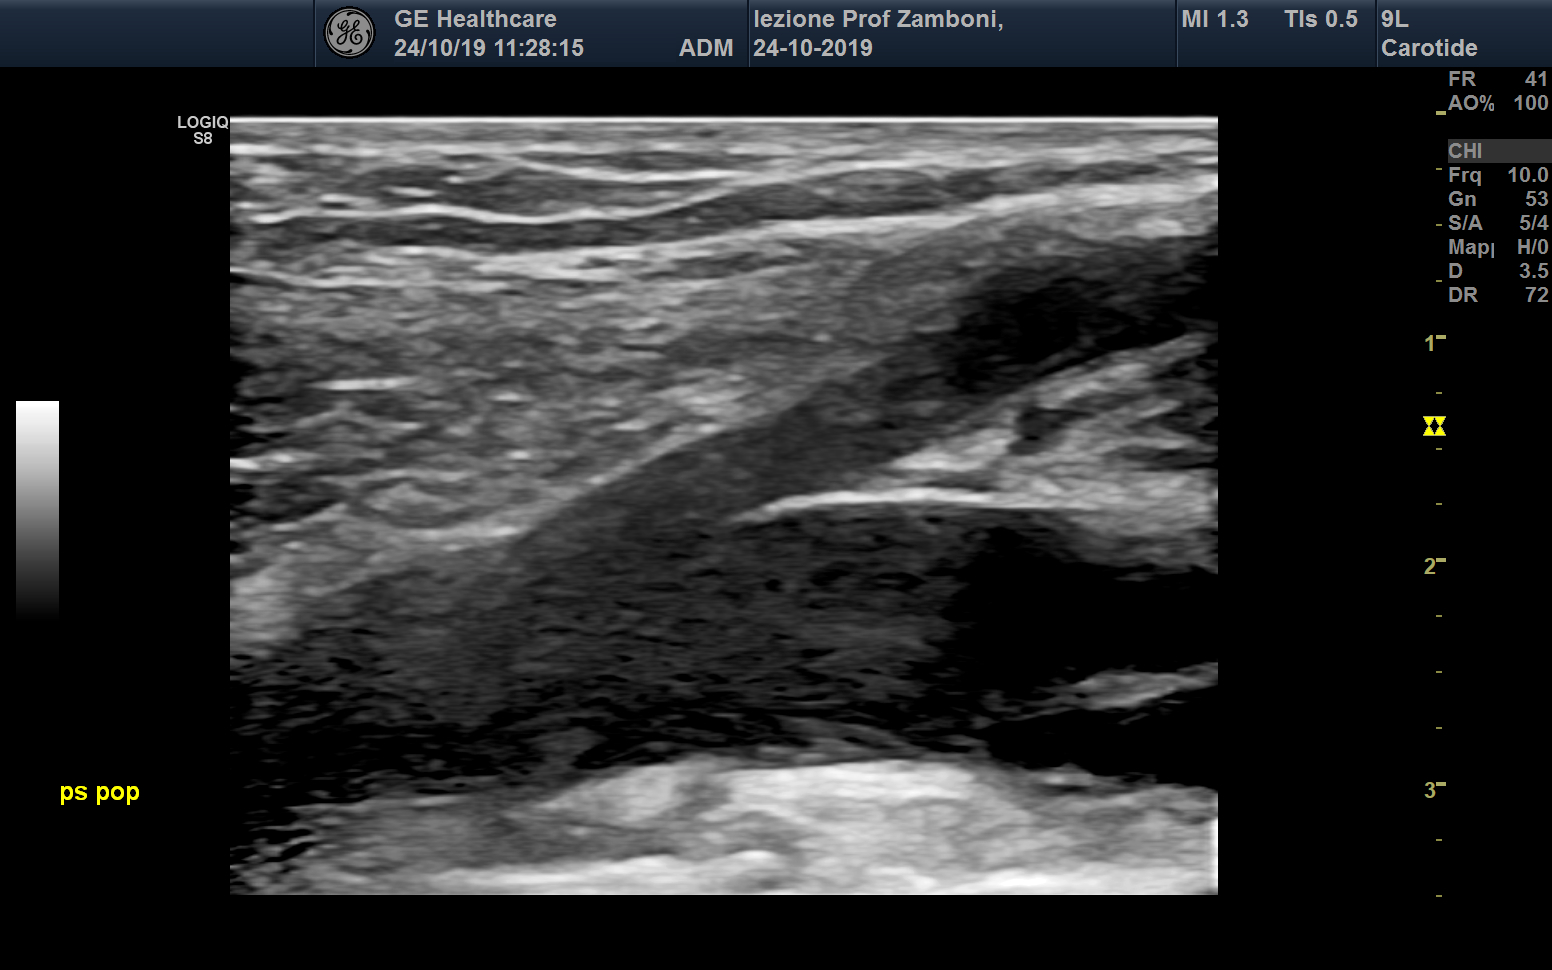

B mode Piccola safene e V. Poplitea

JPEG image icon B mode Piccola safene e V. Poplitea.jpg — JPEG image, 463 kB (474705 bytes)